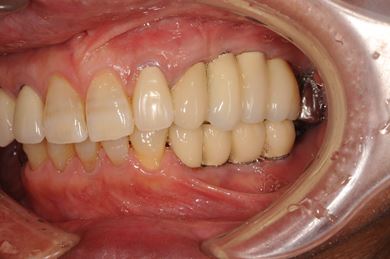

| 性別/年齢 | 男性 / 58歳 | ||||||||||||||||||||||||||||||||

| 主訴 | ブリッジがだめになったため、現在は部分入れ歯を使用しているが、インプラント治療を検討している。 | ||||||||||||||||||||||||||||||||

| 治療方針 | 左上奥の欠損部分をインプラント治療にて、機能的・審美的回復を行う。 | ||||||||||||||||||||||||||||||||

| 治療内容 | インプラント3本(GBR)、ハイブリッドセラミッククラウン3本 | ||||||||||||||||||||||||||||||||

| 総治療費 | 791,520円 | ||||||||||||||||||||||||||||||||

| 治療期間 | 10ヶ月 |